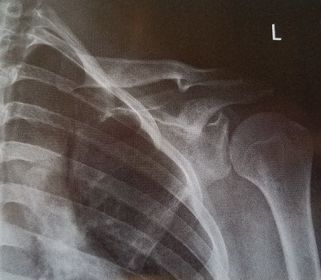

| AP Shoulder internal rotation | the MCP is tilted posteriorly as marked by the superior scapular angle is inferior to the clavicle |

| AP Shoulder | patient is rotated towards the unaffected shoulder: decreased thoracic superimposition over the scapular body |

| AP Shoulder | patient is rotated towards affected side:increased thoracic superimposition over the scapular body |

| Inferosuperior Axiolateral Shoulder | humerus is foreshortened - humeral head is distorted arm is not abducted 90 degrees from body |

| Grashey | Insufficient obliquity |

| Grashey | Excessive obliquity |

| Grashey | MCP is tilted posteriorly |

| AP Shoulder Neutral | ANATOMY: proximal humerus, lateral 2/3 of clavicle, open shoulder joint CRITERIA: humeral epicondyles are 45 degrees to the IR neither tubercle should be seen on the humeral head POSITIONING: CR perpendicular @ 1'' inferior to coracoid process |

| AP Shoulder Internal Rotation | CRITERIA: lesser tubercle in profile medially POSITIONING: CR perpendicular @ 1'' inferior to coracoid process |

| AP Shoulder External Rotation | CRITERIA: greater tubercle in profile laterally POSITIONING: CR perpendicular @ 1'' inferior to coracoid process |